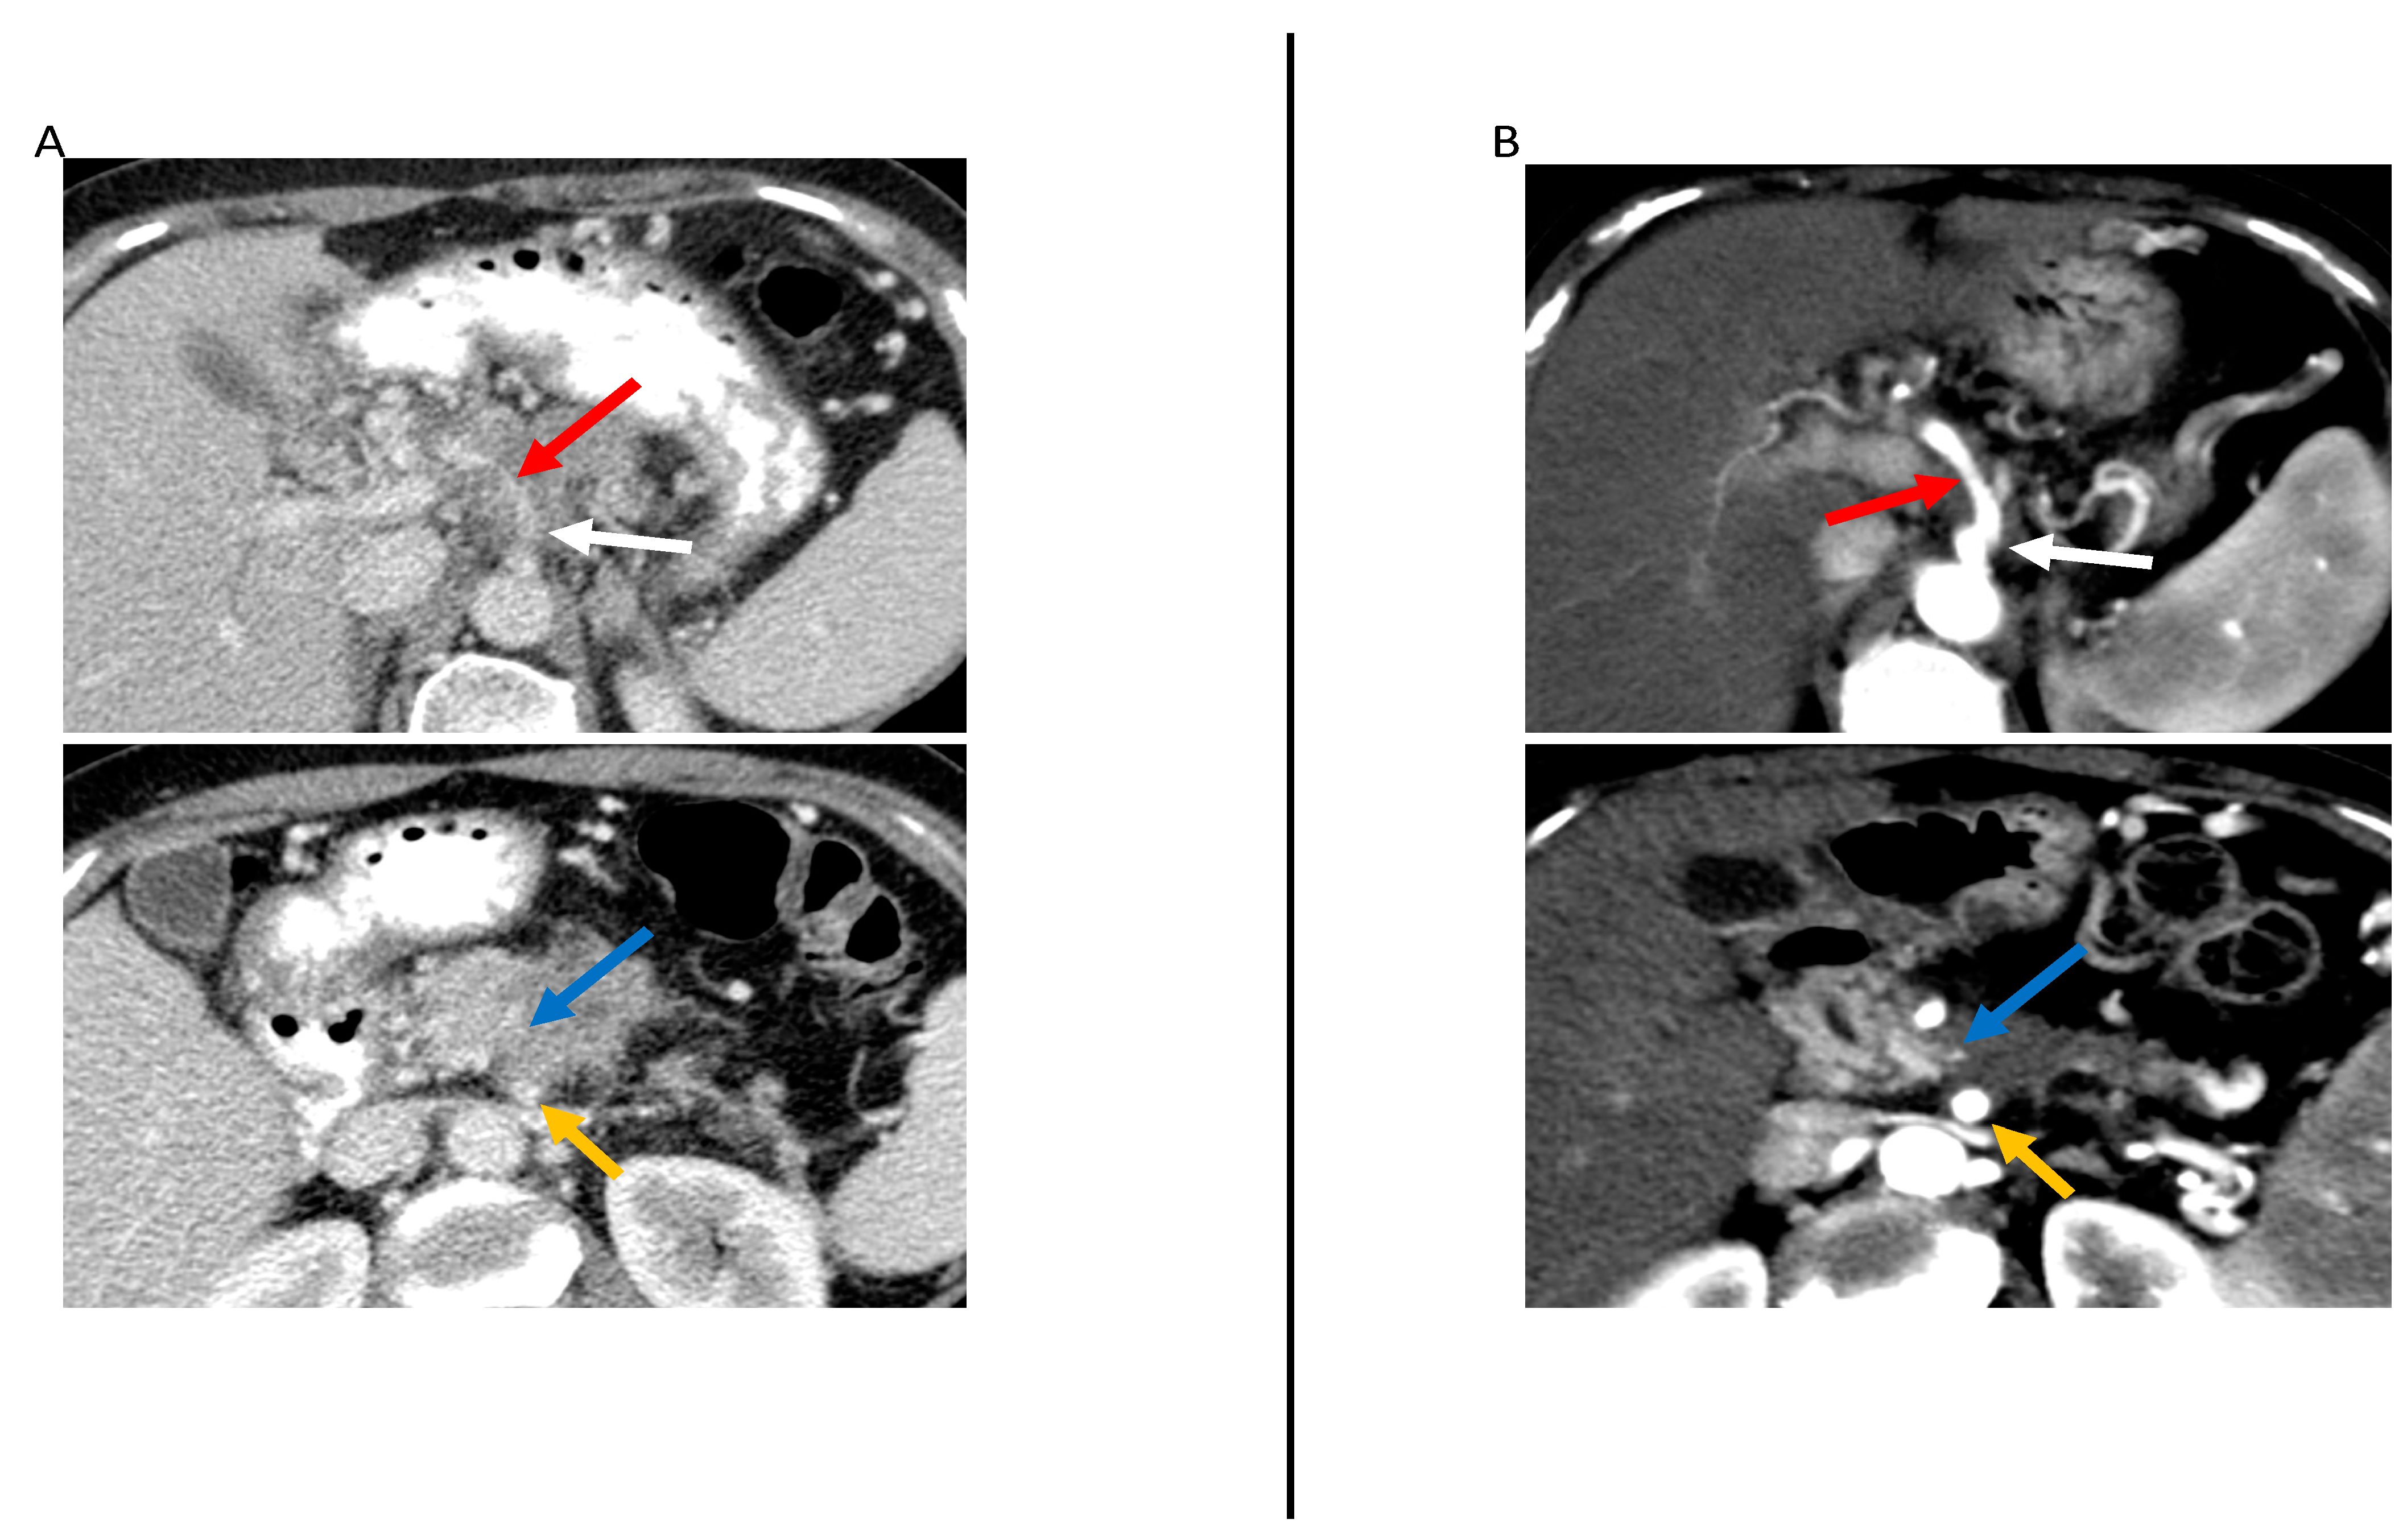

- Rigiroli, F.; Hoye, J.; Lerebours, R.; Lafata, K.J.; Li, C.; Meyer, M.; Lyu, P.; Ding, Y.; Schwartz, F.R.; Mettu, N.B.; et al. CT Radiomic Features of Superior Mesenteric Artery Involvement in Pancreatic Ductal Adenocarcinoma: A Pilot Study. Radiology 2021, 301, 610–622. [Google Scholar] [CrossRef]

| Rigiroli et al. [49], 2021 (U.S.) | 194 | -Chemo -CRT | Resectability status based on NCCN criteria | Semi-automatic, 3D VOIs containing the tumor and perivascular tissue surrounding the SMA | Python | -The model containing five perivessel and tumor radiomic features had an AUC of 0.71 to determine tumor involvement of the SMA, whereas resectability status based on NCCN criteria had an AUC of 0.54. |